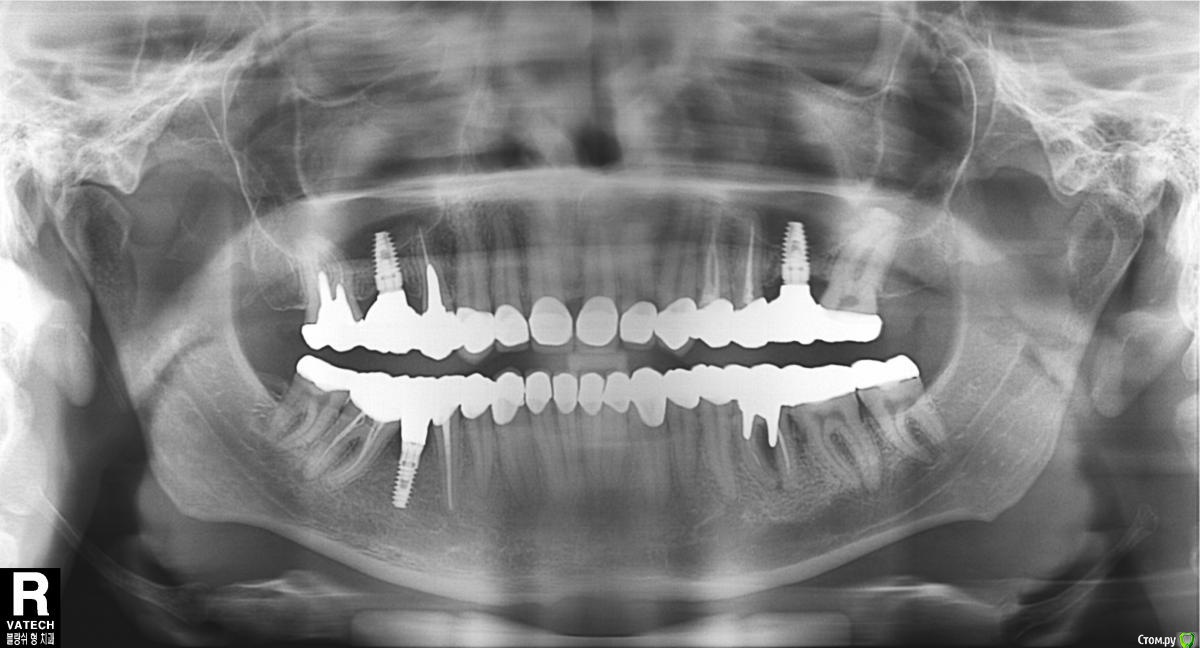

yui Опубликовано 26 мая, 2015 Поделиться Опубликовано 26 мая, 2015 Здравствуйте, Иногда беспокоит нижняя 7ка справа.На нажатие и простукивание не беспокоит.Иногда присутствует что то типо кратковременной реакции на холодное-горячее, причем не ноёт и проходит очень быстро(2-3 секунды), но порядком поддастало уже.Может есть какие либо советы? Рентген прикладываю. Ссылка на комментарий

AlexanderGudkov Опубликовано 26 мая, 2015 Поделиться Опубликовано 26 мая, 2015 На холодное/горячее реагирует скорее всего восьмой справа. В семерке есть проблема с каналами, но таких жалоб это не даст. Слева, кстати в 6 проблемы, может внезапно обостриться 2 Ссылка на комментарий

yui Опубликовано 26 мая, 2015 Автор Поделиться Опубликовано 26 мая, 2015 (изменено) Про 6ку слева в курсе, там риски были заранее известны, доктор предупредил.Про 8ку справа можно поподробней?По ощущениям 8ка совсем не беспокоит.По ощущениям опять же именно 7ка реагирует, но я бы с натяжкой назвал это реакцией, потому как не ноет, и почти мгновенно проходит, и не постоянно. Просто вот именно это "иногда" и подзадолбало, бывает еш чтонибуть и тут реагирует, дальше продолжаешь есть и всё нормально. Коронки все раздельно, то есть не мостами а каждая отдельно, если я правильно понял вопрос. Изменено 26 мая, 2015 пользователем yui Ссылка на комментарий

AlexanderGudkov Опубликовано 26 мая, 2015 Поделиться Опубликовано 26 мая, 2015 В области жевательных зубов справа у вас чувствовать температуру может только восьмой зуб. Ссылка на комментарий

AlexanderGudkov Опубликовано 26 мая, 2015 Поделиться Опубликовано 26 мая, 2015 Да, я знаю что чувствовать может по идее только восьмой, потому как в 7мом каналы пролечены.Но парадокс в том что вот именно 8ой вообще никак не беспокоит и не проявляет себя, а ощущения именно в 7мом, единственное что приходит в голову возможно какие то остаточные реакции? Потому как и сам зуб то реагирует не как болеющий или воспалённый, а как то урывками и непонятно.В любом случае, есть показания для перелечивания седьмого. Возможно, сделав это, жалобы прекратятся. Если нет - заниматься восьмеркой Ссылка на комментарий

yui Опубликовано 26 мая, 2015 Автор Поделиться Опубликовано 26 мая, 2015 Александр, Спасибо за консультацию и совет.Вот думаю стоит ли, очень уж не хочеться вскрывать с виду нормальный зуб, по рентгену если не ошибаюсь по виду там всё нормально. Ссылка на комментарий